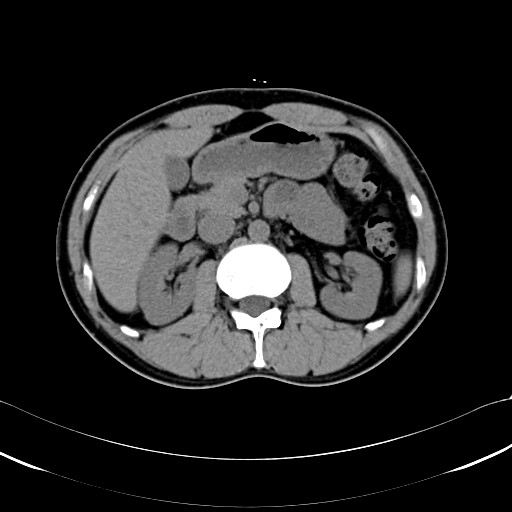

ちなみに2006/11/1。

脂肪がないw